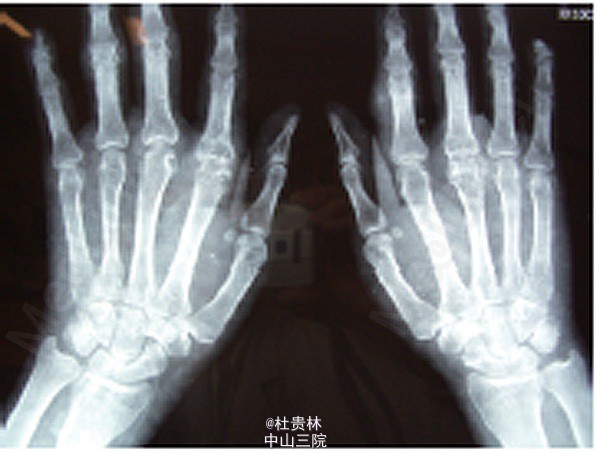

患者男,52岁,因“反复多关节肿痛24年,发现尿检异常、肾功能不全”入院。

贫血貌,双侧眼睑轻度水肿,双耳廓见米粒大小硬结(图1)。双下肢轻度浮肿,双手第一掌指关节明显红肿,皮温 升高,拒触摸。双手掌指关节、双足第一跖趾关节明显变形,活动受限,双手及双足可见数个鸽蛋大小结节,质软 BUN 15 mmol/L,SCr 200μmol/L,血尿酸720 μmol/L。